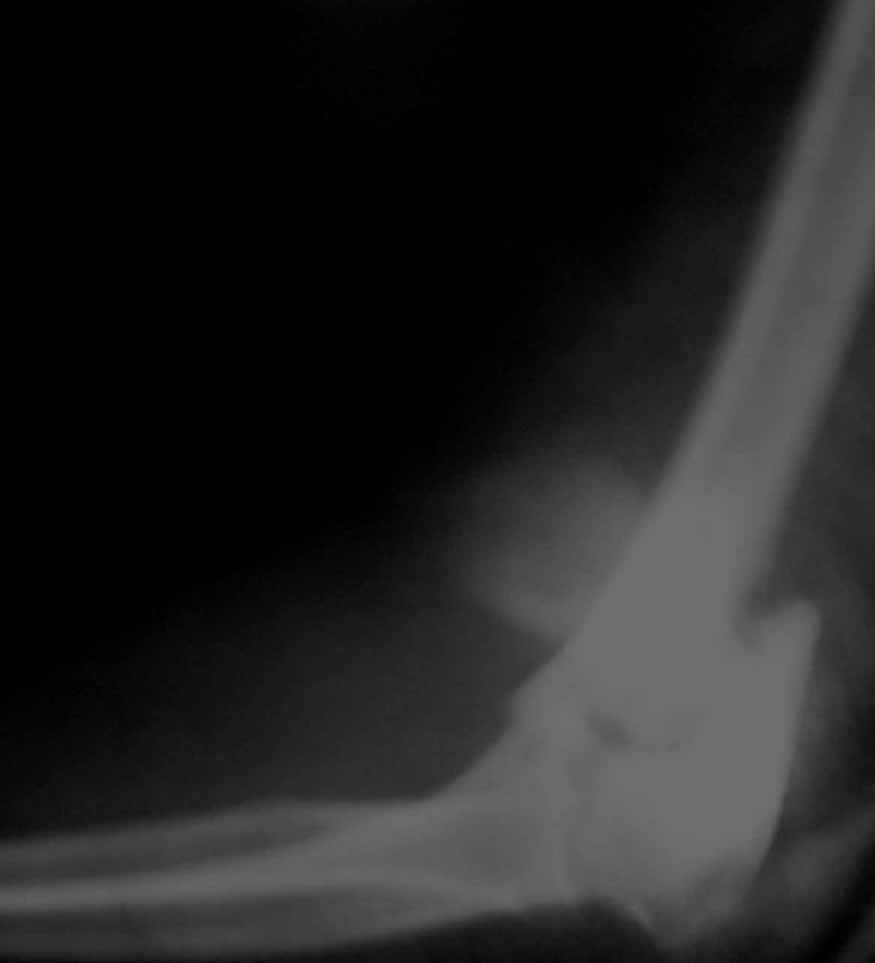

Alexander Artemiev 14 Сентябрь 2005, 16:19

Женщина 42 лет, операция через неделю после перелома.

Д-з - открытый перелом мыщелков со смещзением и локтевой кости

без смещения - падение с лошади.

До операции снимки не очень, тем более в гипсе.

Остеосинтез закрытый (если так можно выразиться), т.е. без

разрезов. Длительность операции - около 1,5 часа со студентом.

6 щелчков ЭОПом.